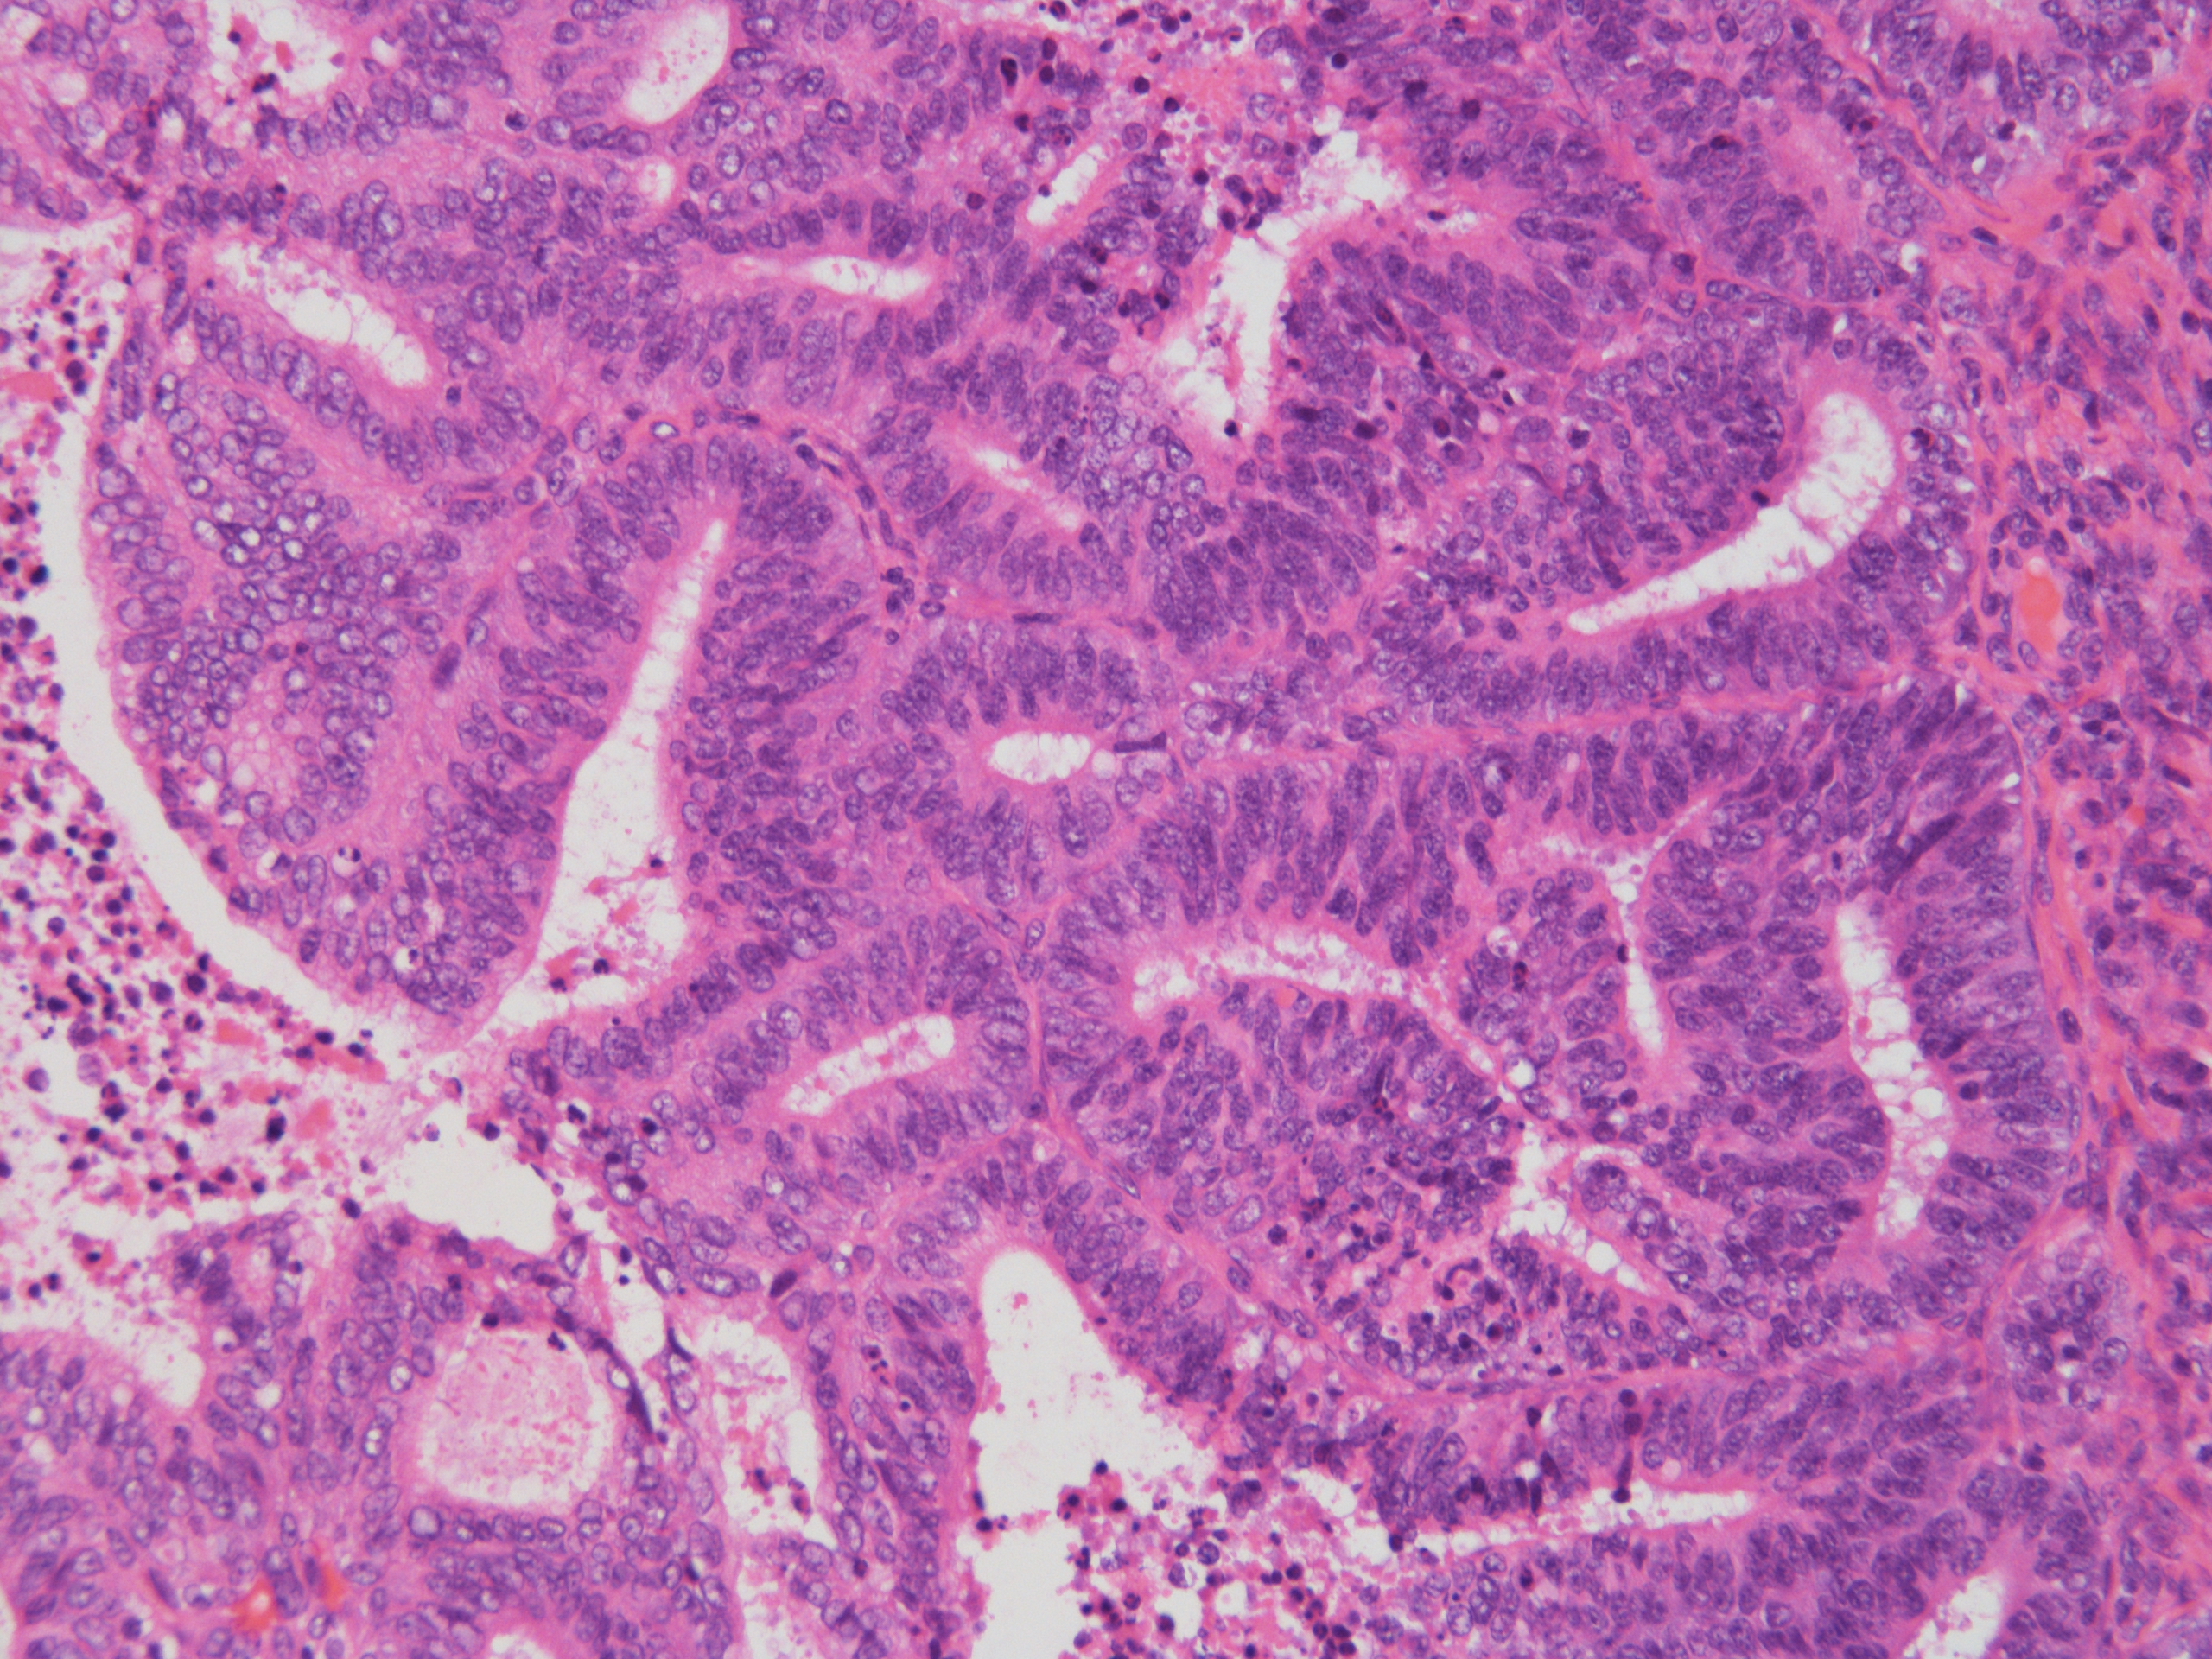

症例1解答、解説、討論記録

解答:類内膜癌(Grade1)

土管状集塊やシート集塊、大型組織様集塊、間質細胞集塊が出現している中に、不整突出集塊をわずかに認めた。

細胞診は、不整形突出集塊が単層で核異型に乏しいため「陰性」と判定したが、

手術標本(子宮摘出)の病理診断は類内膜癌(Grade1)で、手術標本と細胞診の所見に乖離を認めた。

渡辺先生より、細胞診の不整形突集塊は「手術標本で子宮内膜増殖症の所見も認められたので子宮内膜増殖症を見ている可能性がある」

とコメントを頂いた。